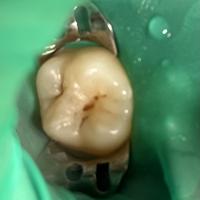

Коротко о бутылочном кариесе